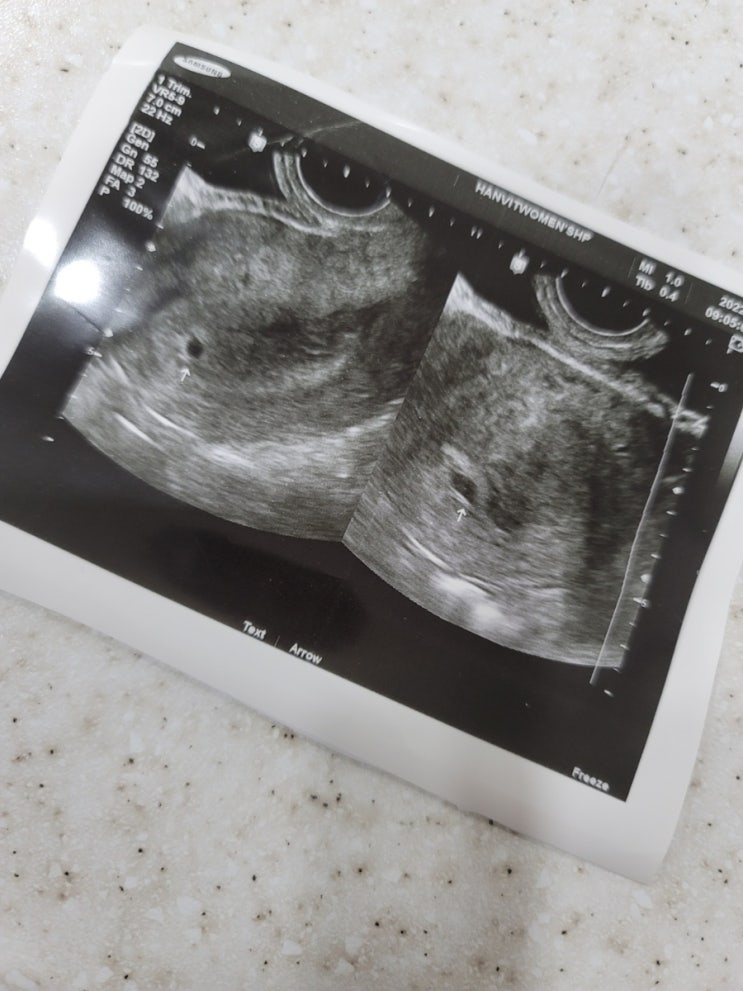

임신 9개월의 기록:-) D-29일 남은 임산부..???

2021년 4월 10일에 결혼해서 21년 가을부터 임신 계획을 세우고 약 7개월(?)만에 2022년 4월 13일 임신 확...